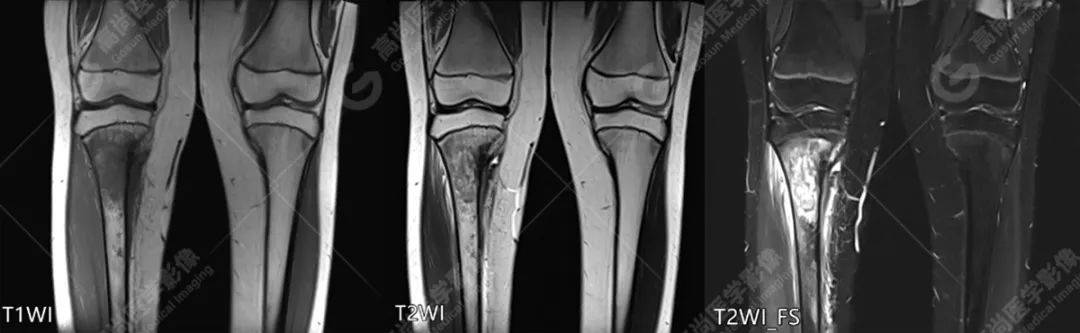

【高尚病例】胫骨骨肉瘤一例_检查_恶性肿瘤_诊断

图片尺寸1080x333